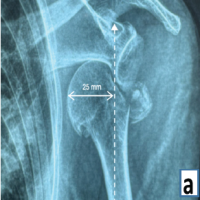

A 49-year-old man sustained a left shoulder fracture dislocation following a road traffic accident. Post-reduction radiograph showed a bony fragment and computed tomography (CT) revealed a bony Bankart lesion at the anteroinferior part of the glenoid articular surface along with an atypical Hill Sachs lesion and a non-displaced greater tuberosity fracture (Fig. 1). The size of the bony fragment was 35% of the glenoid surface area on the 3-dimensional CT (3D CT) and therefore, we decided to add screw fixation along with suture-assisted reduction by arthroscopic reduction and internal fixation of the bony Bankart lesion.

Once all sutures were passed, each pair of sutures were retrieved and tied in a sequential fashion beginning with the inferior-most sutures, working anterior-superiorly, thereby achieving anatomic reduction of the bony fragment. A cannula was inserted into the trans-subscapularis portal and a 3.5 mm × 34 mm cannulated cancellous Latarjet screw was used to fix and give compression to the bony fragment after confirmation of reduction of articular surface. The length of the screw was predetermined using preoperative CT scan (Fig. 4, 5, 6).